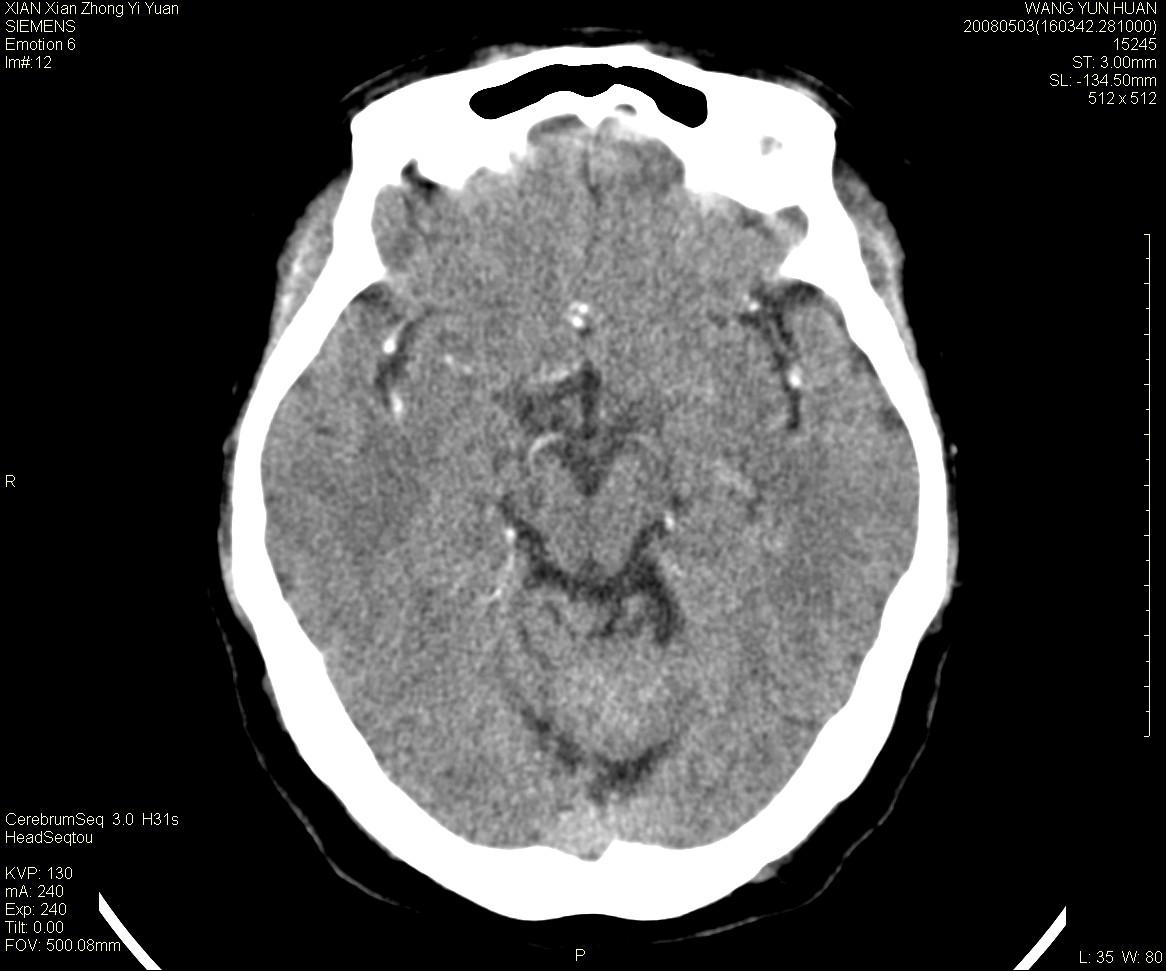

病灶显示轻度强化,ct增加4hu左右,大家看是什么肿瘤.

强化后动脉期及延迟2分钟,五分钟图像

小脑蚓部占位,考虑脑膜瘤。增强吧

小脑蚓部囊型肿块,内有实性结节及钙化点。增强后囊壁及结节轻度强化。

考虑蚓部星形细胞瘤(ⅱ级可能性大)。

小脑蚓部肿块,周围无明显占位效应及水肿带,增强轻度强化,考虑低分级星形细胞瘤。